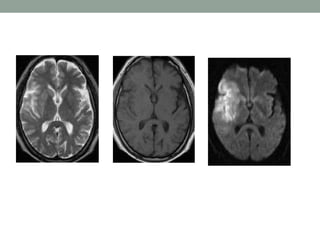

• T2-weighted imaging is well suited for lesion detection in

the brain because most lesions appear hyperintense with

this sequence.

• However CSF also appears hyperintense on T2-weighted

spin-echo (SE) images.

• Therefore, lesions at CSF interfaces, such as cortical sulci

and ventricles, may be mistaken for extensions of CSF or

partial volume effects.

• FLAIR imaging suppresses signal from free water in CSF

and maintains hyperintense lesion contrast.

• FLAIR sequences are particularly useful in evaluation of

MS, infarcts, SAH

65 year male- acute Rt ACA Infarct